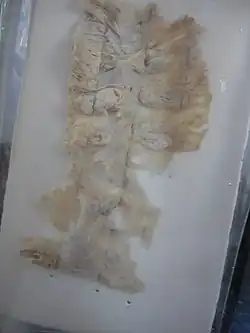

.jpg) Amoebae in a colon biopsy from a case of amoebic dysentery.

Amoebae in a colon biopsy from a case of amoebic dysentery. -